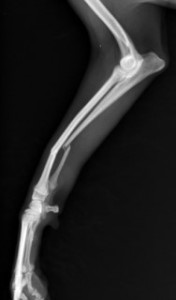

手術前

手術後

ロッキングプレートで整復しました。